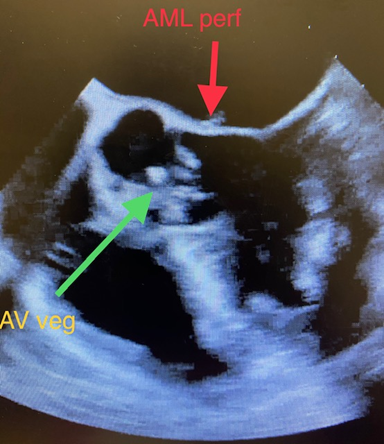

• Infection of the valves can affect both mitral and aortic valve simultaneously (figure 3).